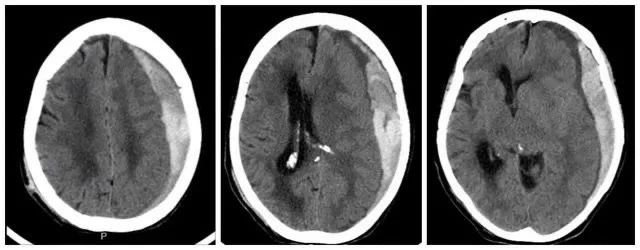

硬膜下血肿是指颅内出血血液积聚在硬脑膜下腔,在颅内血肿中发生率最高。根据伤后血肿发生的时间,分为急性硬膜下血肿(伤后3天以内)、亚急性硬膜下血肿(伤后3天至3周内发生)和慢性硬膜下血肿(伤后3周以上)。

诊断硬膜下血肿最优检查是头颅CT,头颅CT很清晰的可以看到血肿量多少,中线移位情况,脑水肿情况,是否合并脑疝形成等;同时头颅CT检查速度快,经济性也挺好。